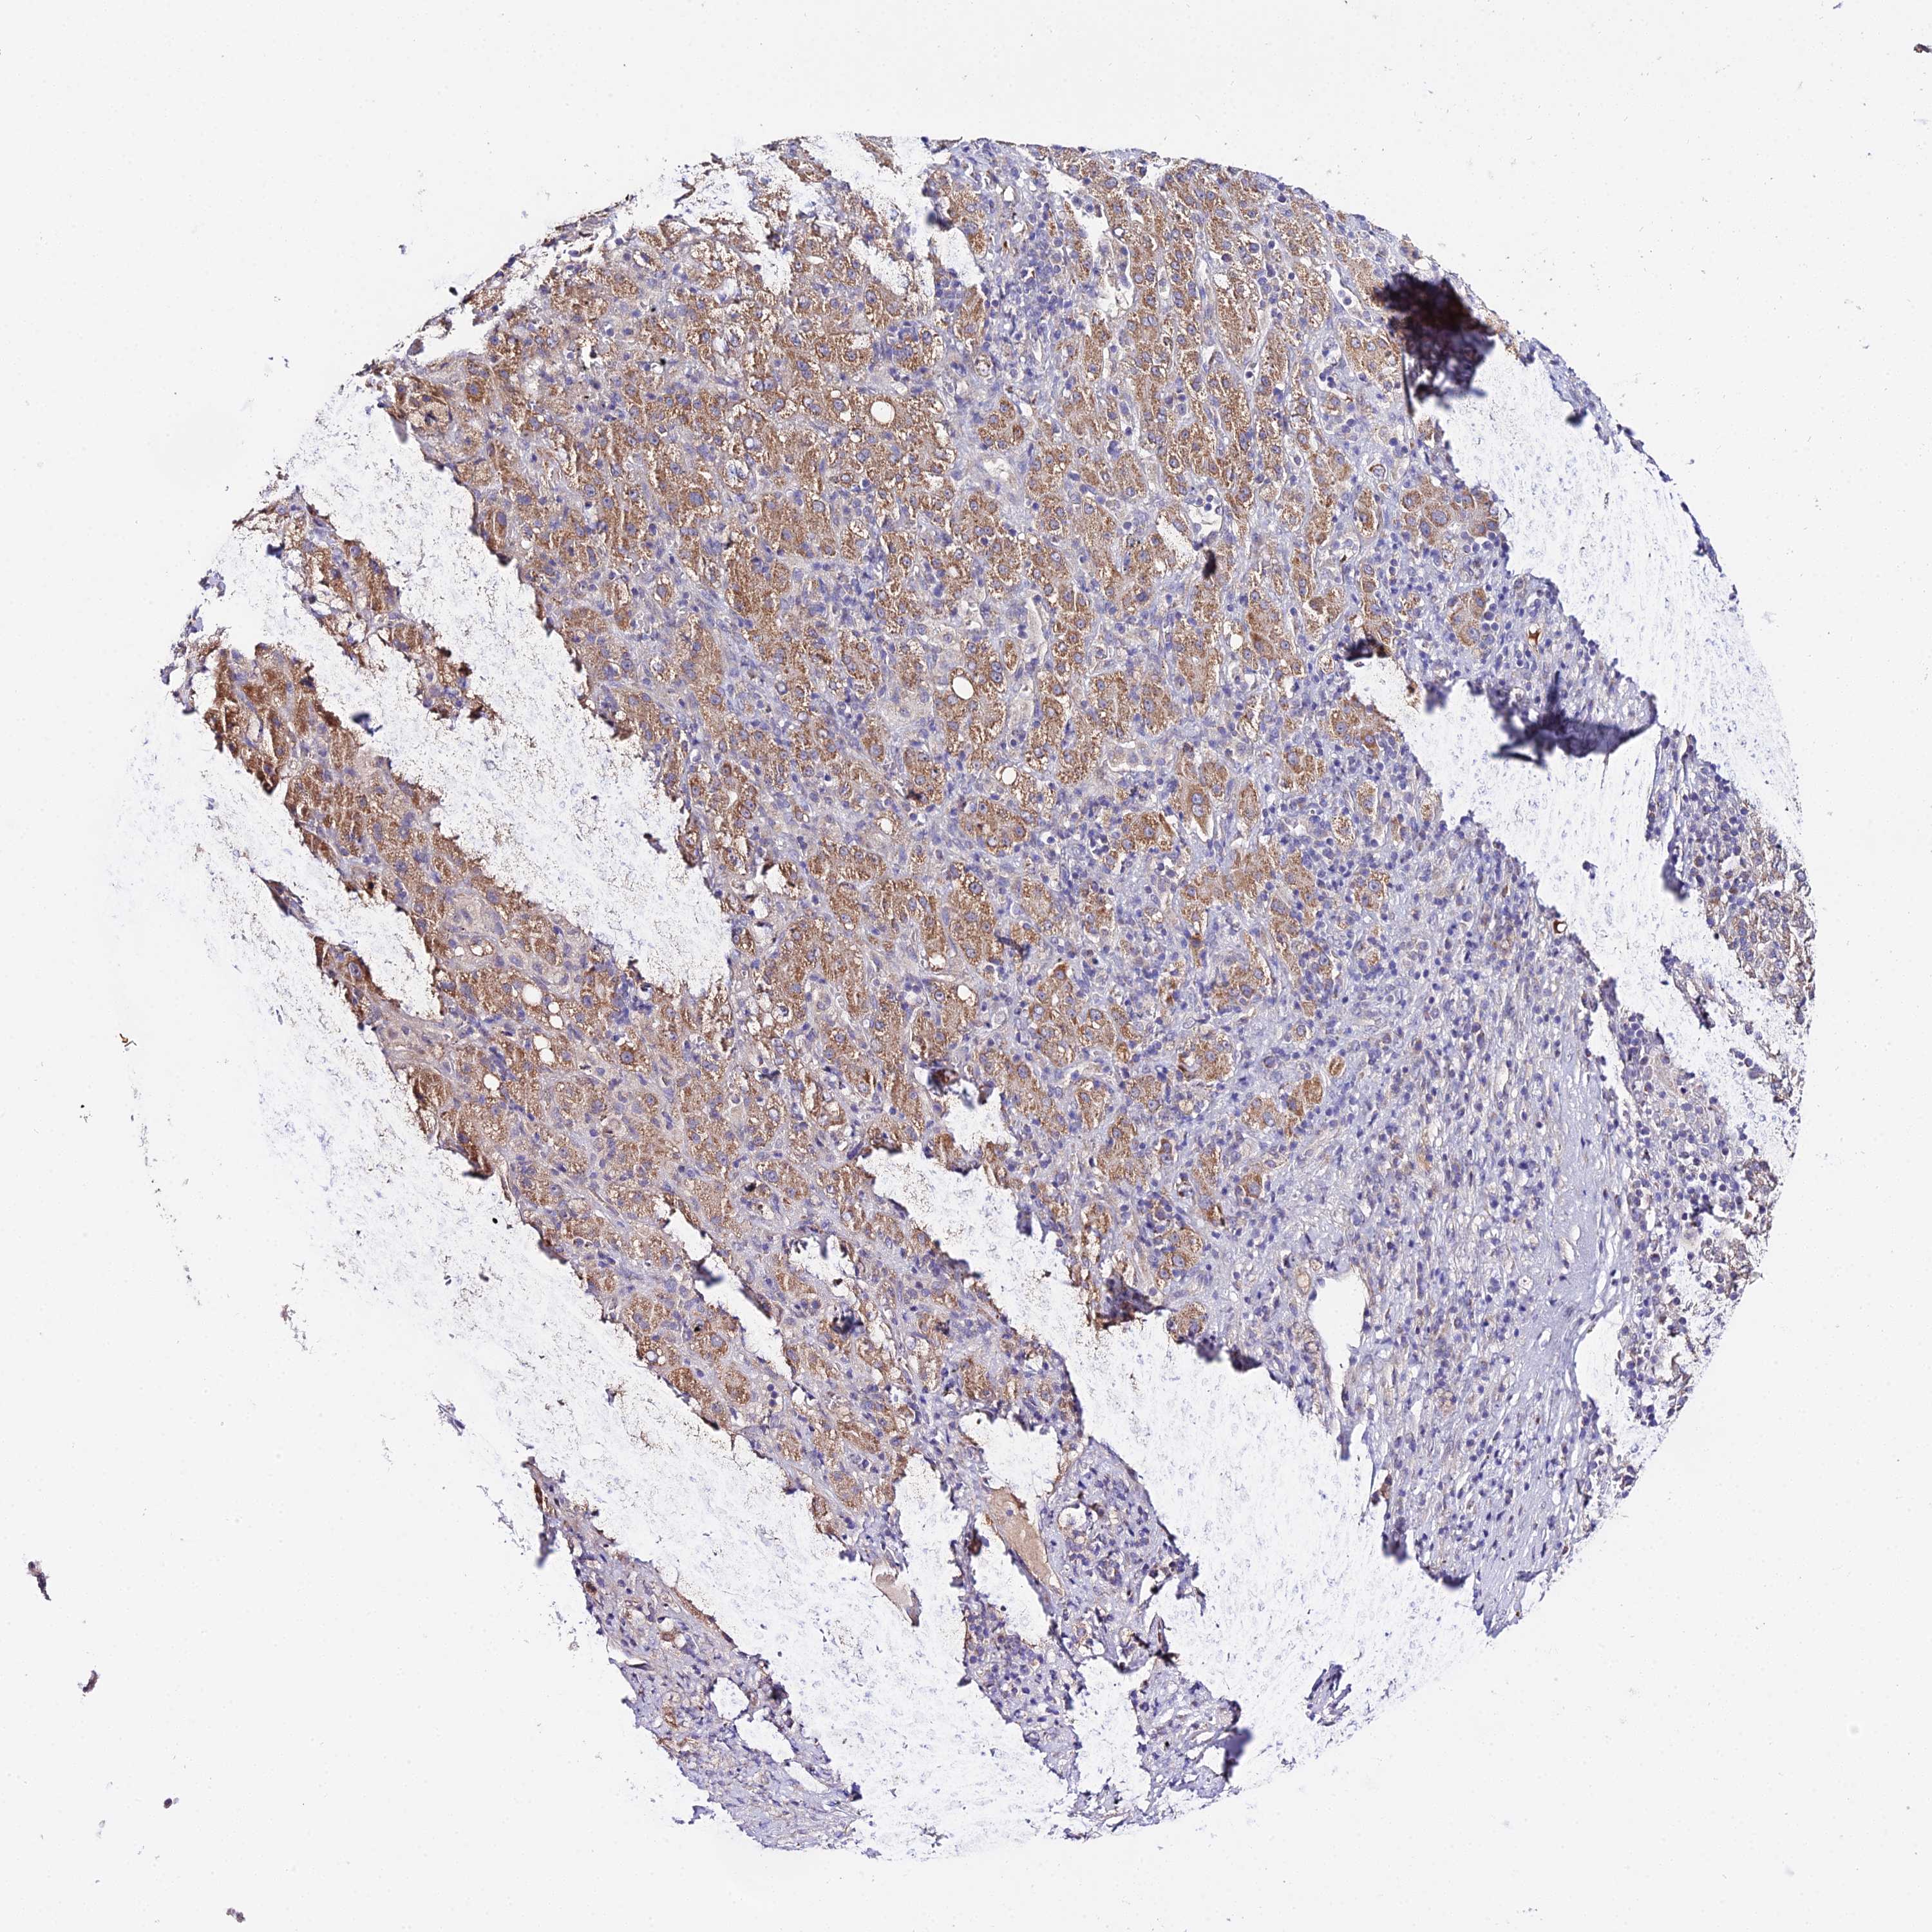

LIVER CANCER - Protein expressioni

A mouse-over function shows sample information and annotation data. Click on an image to view it in a full screen mode. Samples can be filtered based on level of antibody staining by selecting one or several of the following categories: high, medium, low and not detected. The assay and annotation is described here.

Note that samples used for immunohistochemistry by the Human Protein Atlas do not correspond to samples in the TCGA dataset.

Antibody stainingi

Antibody staining in the annotated cell types in the current human tissue is reported as not detected, low, medium, or high, based on conventional immunohistochemistry profiling in selected tissues. This score is based on the combination of the staining intensity and fraction of stained cells.

Each image is clickable and will lead to virtual microscopy that enables deeper exploration of all samples and also displays staining intensity scores, fraction scores and subcellular localization as well as patient and tissue information for each sample.

Antibody HPA042994

Staining

High

Medium

Low

Not detected

Intensity

Strong

Moderate

Weak

Negative

Quantity

>75%

75%-25%

<25%

None

Location

Nuclear

Cytoplasmic/membranous

Cytoplasmic/membranous,nuclear

Cholangiocarcinoma

Carcinoma, Hepatocellular, NOS